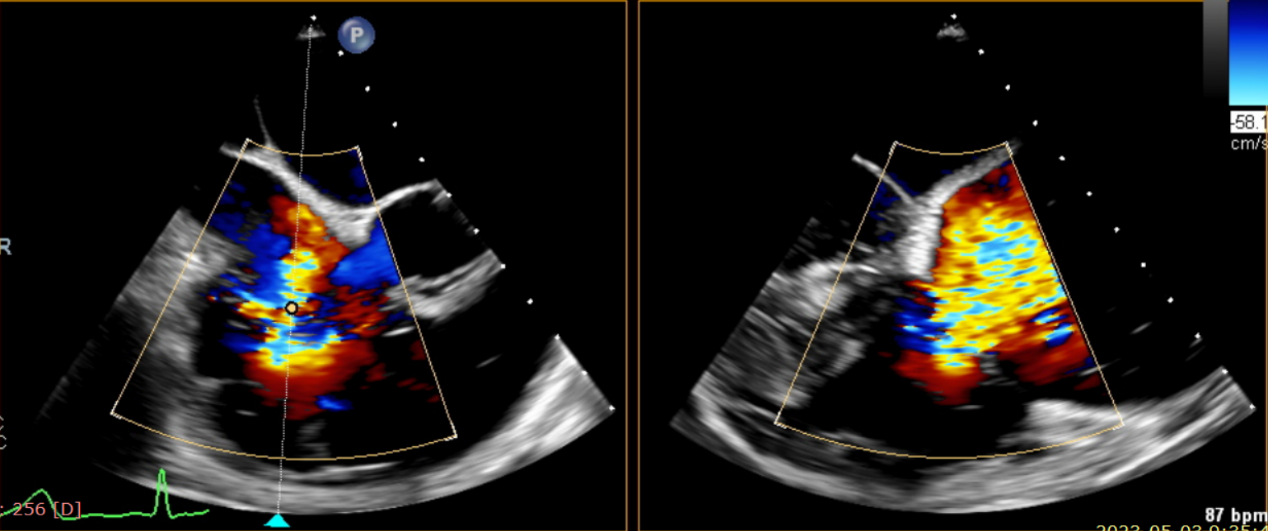

術前超聲提示大量三尖瓣反流

術中輸送器在超聲引導下調整位置

術后超聲提示僅殘余輕微瓣周漏

術后Azeem Latib教授對LuX-Valve Plus經血管三尖瓣置換系統的器械性能和治療效果大為稱贊,并且認為LuX-Valve Plus的手術體驗非常好。從治療效果來看,術后即刻超聲顯示三尖瓣反流幾乎完全消失,血流動力學改善顯著,患者恢復快。在面對復雜解剖結構、超聲影像質量不佳、有起搏導線干擾時,Lux-Valve Plus也體現了極強的適應性。Thomas Modine教授參與了術中指導,他同樣再次肯定了LuX-Valve Plus術中操作的便捷性,認為LuX-Valve Plus容錯率高,對術中影像的依賴小,并表達了后期希望可以更多地應用LuX-Valve Plus三尖瓣置換系統于臨床實踐,讓更多的三尖瓣重度反流患者盡早獲益,改善預后。